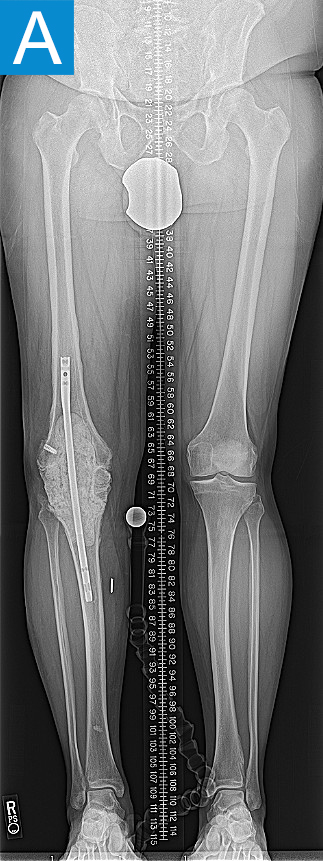

A 47-year-old man was referred for management of end-stage periprosthetic joint infection (PJI) of the right knee. The knee had undergone 20+ surgeries over 15 years, starting with anterior cruciate ligament reconstruction, followed by total knee arthroplasty that was complicated by patellar tendon rupture and subsequent infection. After 3 failed 2-stage knee revisions he presented with a painful static cement spacer on antibiotic suppression (Figure 1a). His arthroplasty surgeons recommended knee arthrodesis or above-knee amputation. The patient was familiar with knee fusion, given his static spacers, and elected for amputation. He was otherwise healthy and desired a high level of function with an amputation; after discussing the risks and benefits of osseointegration limb reconstruction versus a traditional socket prosthesis, he decided on osseointegration.

Standing radiographs showed periosteal reaction to the distal femoral isthmus, and given the chronicity of his infections the decision was made to stage the transfemoral amputation and osseointegration implant insertion (Figure 1b). During the amputation, the tibial and peroneal nerves underwent targeted muscle reinnervation to the motor branches of the medial and lateral hamstrings, respectively. Cement mixed with tobramycin and vancomycin was placed in the femoral canal, and the remaining musculature was purse stringed around the residual femur. His proximal cultures were negative, and so no further antibiotic treatment was given. Approximately 8 weeks later, the antibiotic spacer was removed and a press fit femoral osseointegration implant was placed in a percutaneous procedure (Figure 2a). Cultures of the canal remained negative.

Figure 1. Preoperative X-rays show (A) static cement spacer on antibiotic suppression and (B) an antibiotic cement spacer in the residual femur.